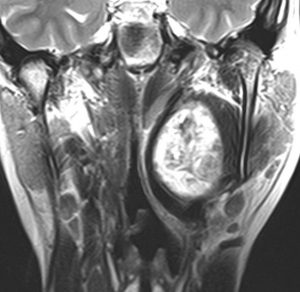

症例:頸静脈孔から頭蓋内へのもの

頸静脈孔を中心に頭蓋底骨の破壊 erosionがみられます。小脳延髄角部に進展して延髄を圧迫しています。聴神経を圧迫して聴力低下で発見された,迷走神経鞘腫です。頸静脈孔内発生のものは脳槽内の迷走神経根から腫瘍を剥離することができます。

手術直後のMRIです。頸静脈孔より深い位置にある腫瘍まで摘出しようとすると,舌咽,迷走,副神経を損傷しますから,最深部の部分だけ残して摘出しました。

手術後14年が経過しますが,無治療で残存腫瘍は縮小しました。術後神経鞘腫の自然経過ではよく観られることです。

ですから,無理して全摘出しない。